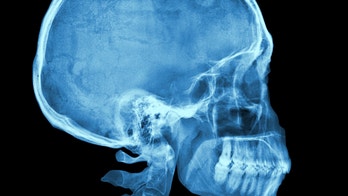

July 21, 2016 Concussions show effects on brain years after injury, study finds Concussion injuries may show up in the brain years after the initial diagnosis, found a new study of college athletes.

July 11, 2016 Data suggest increase in reported youth concussions; upwards of 500 percent since 2010 Two new data sets suggest youth concussions may be more common than previously thought.

June 20, 2016 Nearly 2M concussions in kids' sports, play yearly? Nearly 2 million concussions from sports or play activities occur in U.S. children and teens each year and many receive no treatment, according to a new study.

June 8, 2016 Muhammad Ali's death: Can head injuries cause Parkinson's? Boxing champion Muhammad Ali lived with Parkinson's disease for three decades before his death on Friday (June 3) at the age of 74, and many have wondered whether Ali's boxing career caused him to develop the neurological disorder.

June 3, 2016 Former internationals to take part in concussion study More than 100 former rugby internationals have agreed to take part in a unique scientific study on the effects of concussion on brain health to increase player safety standards in the sport, the Rugby Football Union (RFU) has said.

June 2, 2016 CTE research moves on, even without the NFL's money Researchers are moving ahead with efforts to develop a diagnostic test for chronic traumatic encephalopathy — even without the NFL's help.